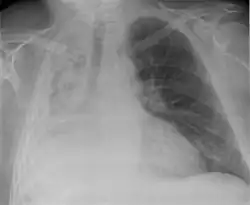

Atelectasis.

May have no signs and symptoms or they may include:[4]